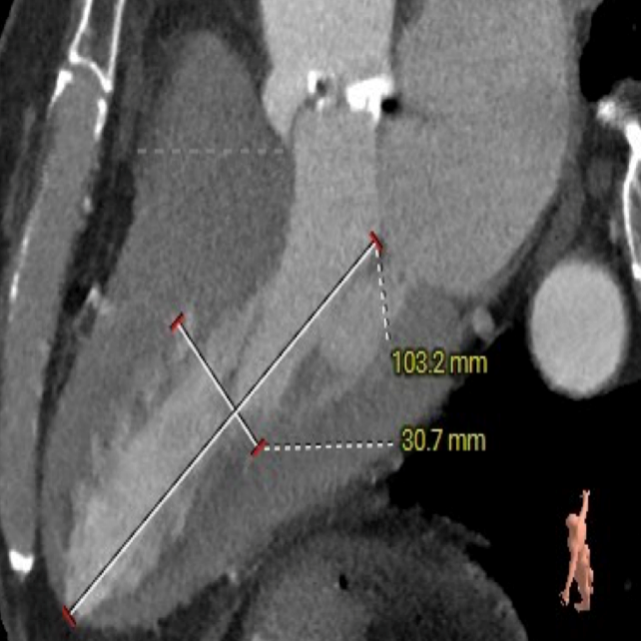

病例特点

该患者为一例重度AS患者,双侧股动脉见环形钙化,外周入路挑战较大,手术风险高。主动脉瓣环水平夹角67度,横位心,假体瓣膜释放后有位移可能。

入路血管内径偏小,双侧髂总动脉血管环形钙化,内径小,存在血管夹层风险。

瓣环水平夹角

主动脉瓣瓣环周长66.2,平均周长径 21.1mm,SOV:32.2mm*36.4mm*34.1mm,瓣叶增厚,瓣上钙化分布不均,主动脉瓣环水平夹角67度,横位心。